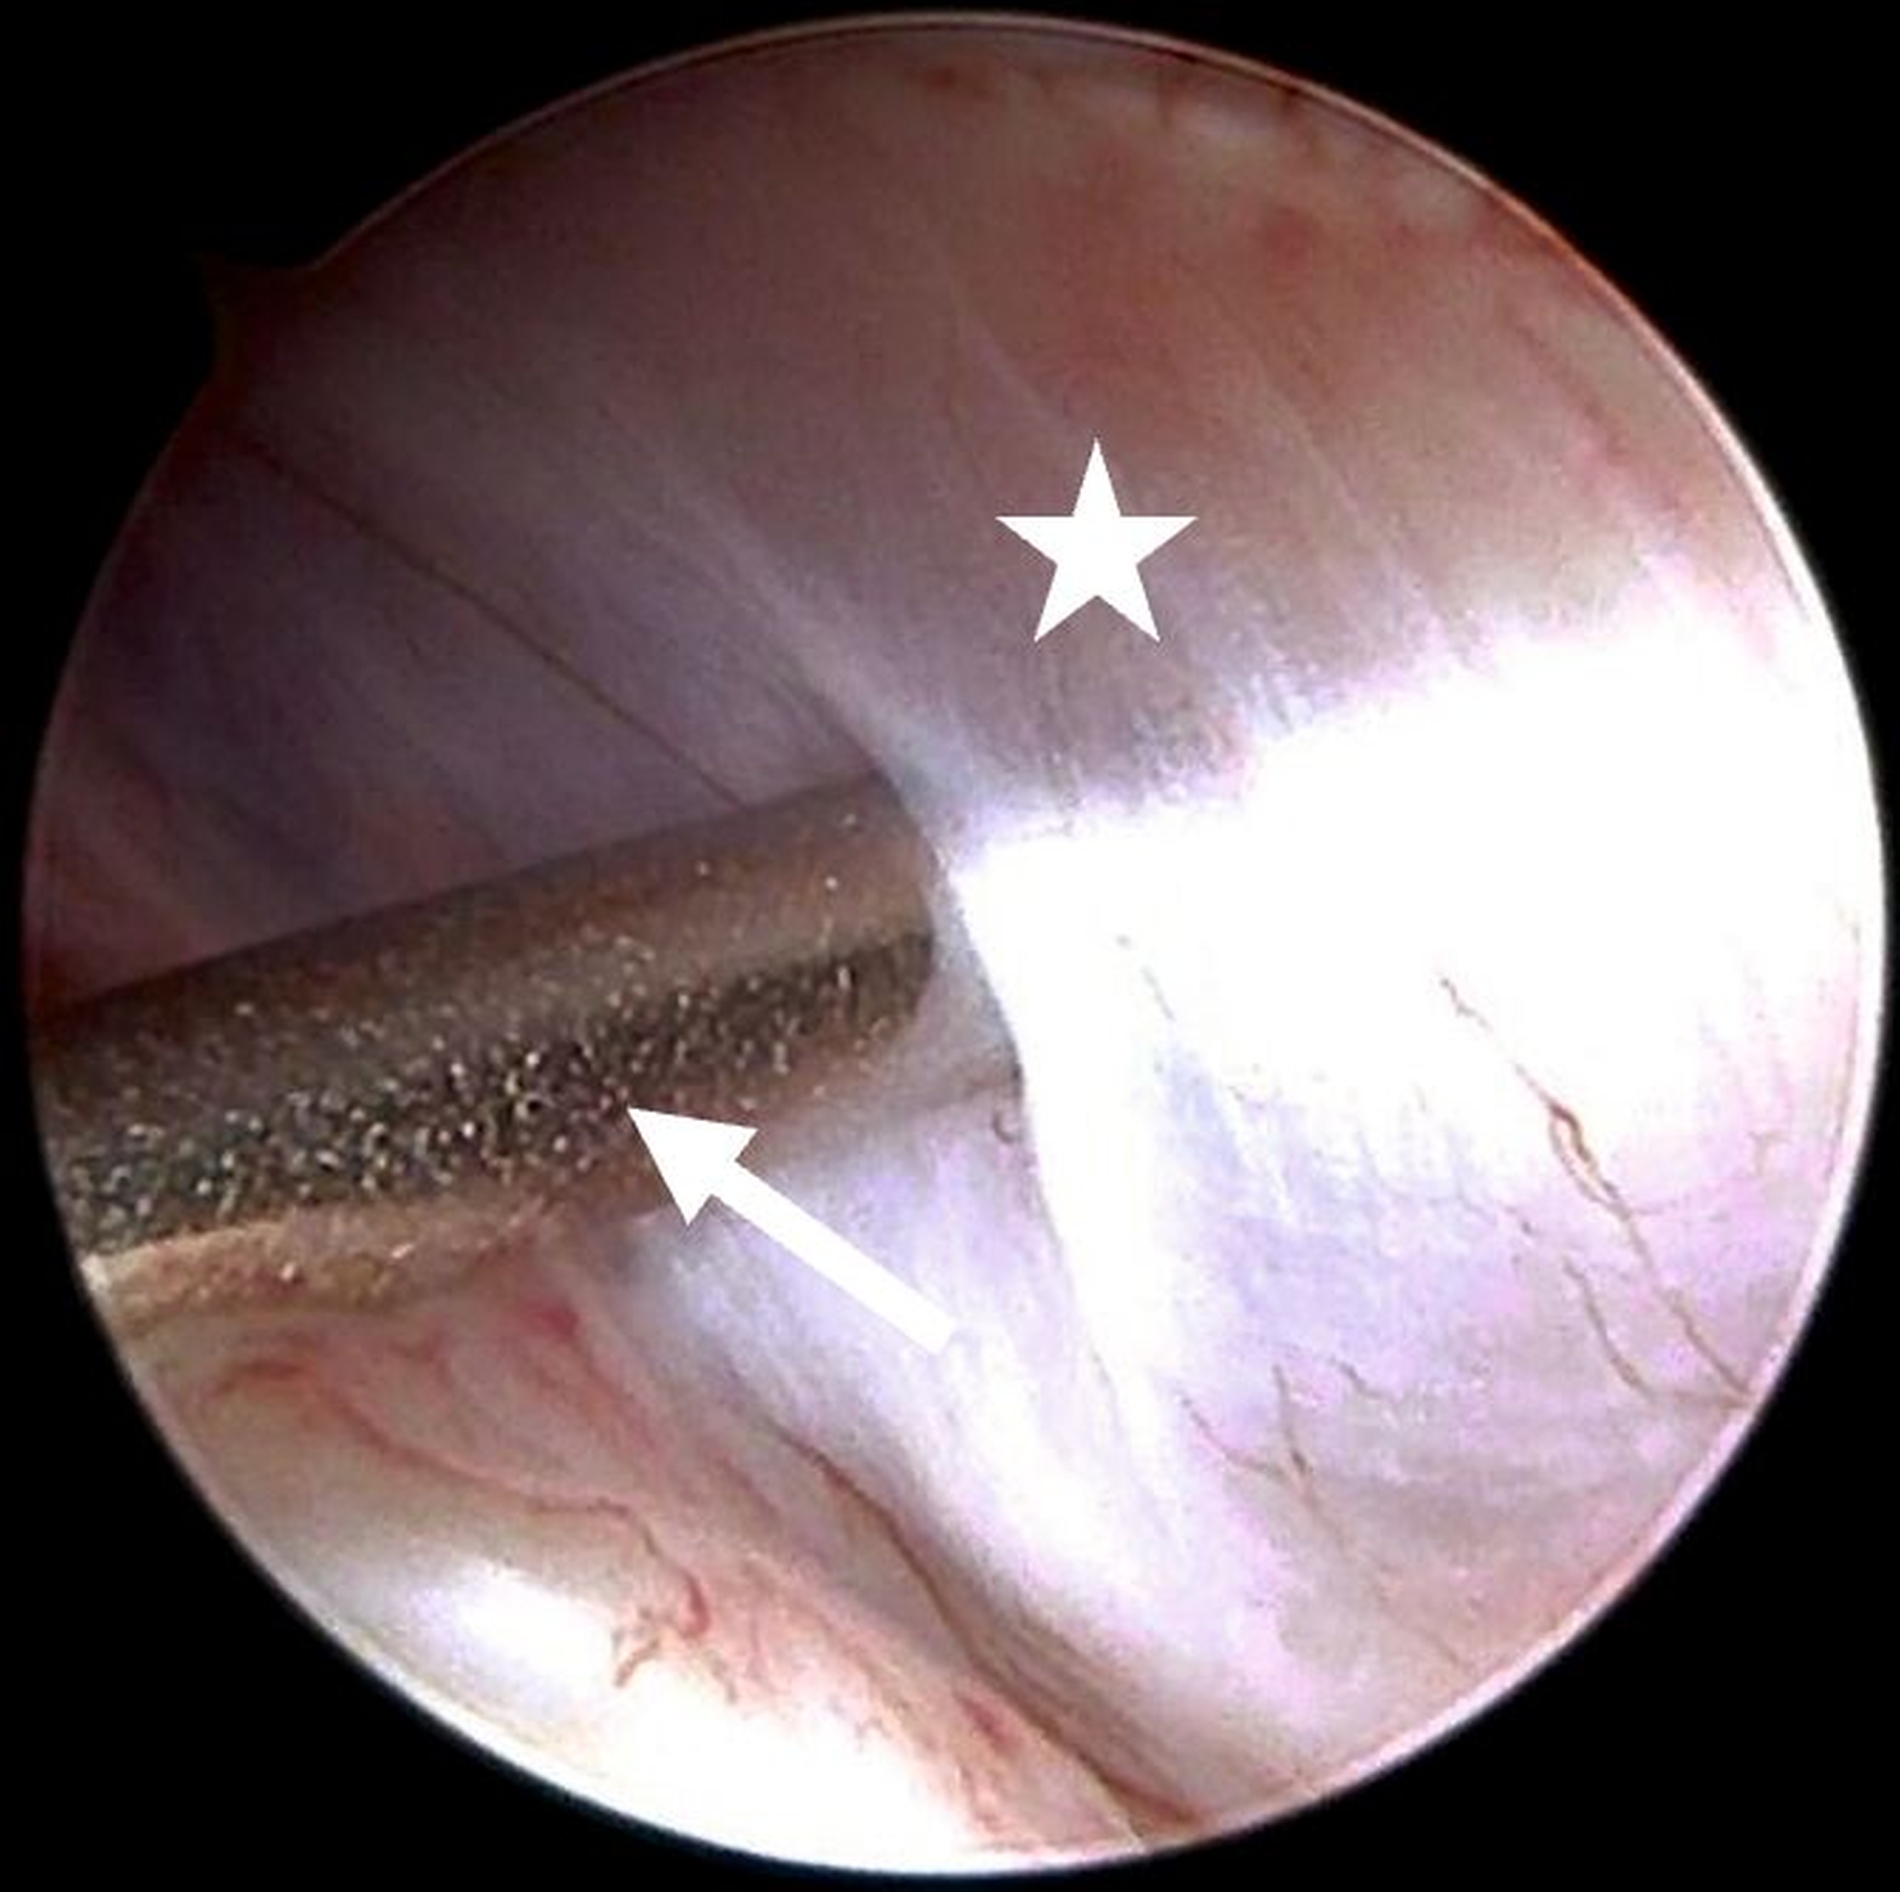

Die Level-II- (Abbildung 4a) beziehungsweisedie Level-III-Arthroskopie beinhalten zusätzlich einen zweiten beziehungsweise einen dritten Zugang über den beispielsweise Verwachsungen entfernt (Abbildung 4b) oder auch Biopsien entnommen werden können. Darüber hinaus ermöglichen diese die Durchführung eines sogenannten „anterior release“ (Abbildung 5). Darunter versteht man das arthroskopische Durchtrennen des vorderen Aufhängungsbandes des Diskus, wodurch dessen Beweglichkeit verbessert werden kann. Auf diese Weise kann der Diskus (unter anschließender konservativer Therapie) wieder in eine physiologischere Position zurückgleiten. Darüber hinaus können auch weiterführende Eingriffe wie Diskopexien durchgeführt werden, also die arthroskopisch gestützte Reposition und Fixation des Diskus in anatomisch korrekter Position [McCain, 1988].

Für intraartikuläre Eingriffe wird häufig die sogenannte Coblation-Technik genutzt (Coblation: Kofferwort aus Controlled Ablation). Diese Technik steht für ein minimalinvasives chirurgisches Verfahren, mit dem durch ein Niedrigtemperaturplasma Gewebe abgetragen werden kann. Im Gegensatz zu thermischen Verfahren wie Laser oder Elektrokaustik arbeitet die Coblation mit Temperaturen zwischen nur 40 bis 70 Grad Celsius. Dadurch kann Gewebe präzise entfernt werden, ohne dass umliegende Strukturen (durch zu hohe Temperaturen) geschädigt werden [Chen et al., 2010].